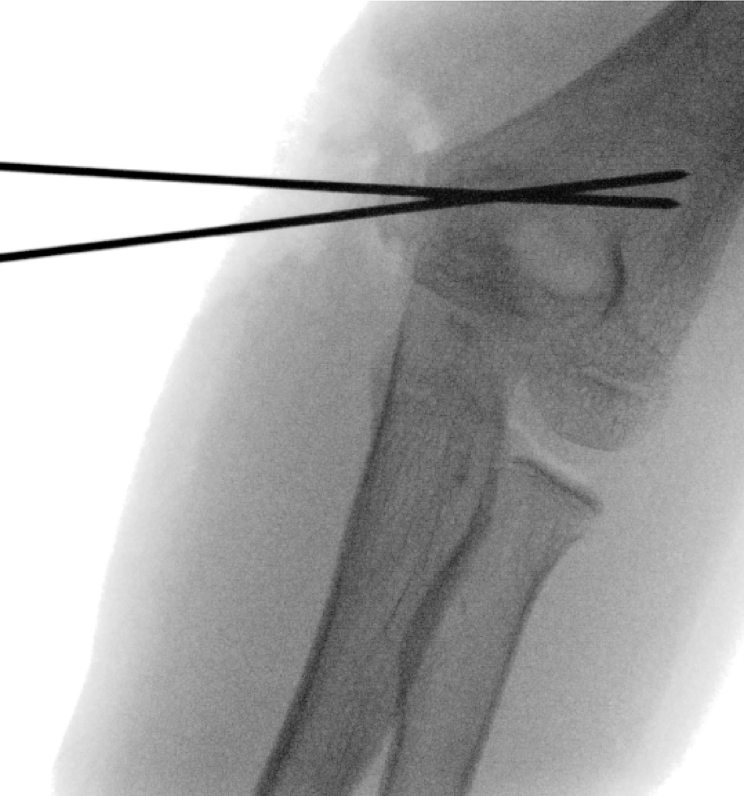

Figure 12. Intraoperative films for Case 4.